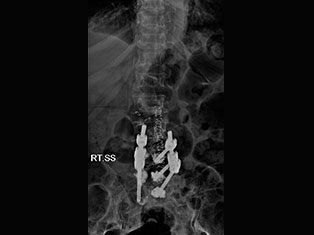

Spinal Tumors

A spinal tumor is a growth that develops within your spinal canal or within the bones of your spine. A spinal cord tumor, also called an intradural tumor, is a spinal tumor that that begins within the spinal cord or the covering.